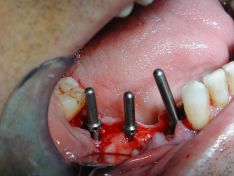

Effettuate le estrazioni, in un secondo momento (si è optato per un inserimento di impianti post-estrattivi differiti o ritardati, cioè dopo 4 settimane), si è proceduto all'intervento chirurgico: preparazione dei siti implantari mini-invasiva (sfruttando la guida fornita dagli alveoli dove prima alloggiavano gli elementi dentari estrattti), inserimento di tre impianti (in zona 47 - 45 - 44), applicazione di biomateriale per riempire gli spazi vuoti attorno e fra gli impianti (procedura di rigenerazione ossea - GBR, allo scopo di favorire appunto il mantenimento e la rigenerazione di nuovo tessuto osseo attorno agli impianti), sutura.